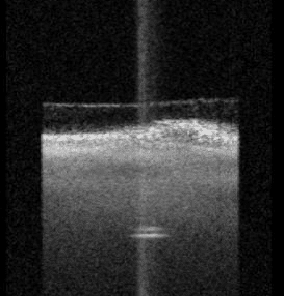

The "dynamic panoramic ocular axis imaging" method provides real-time visualization. It monitors fixation and displays macular fovea fixation at the same time. Eye parameters can be obtained at the same eye position, fastens acquisition and improves measurement accuracy and repeatability. Real-time panoramic images from cornea to retina are obtained, the measurement data can be confirmed.

• Get fewer refractive surprises: Detect unusual eye geometries & poor fixation, providing a full-length OCT image showing anatomical details of the eye on a longitudinal cut through the entire eye.

All measurement calipers are shown on the patented Cornea-to-Retina Scan allowing you to visually verify what structure has been measured.

Panoramic axial imaging